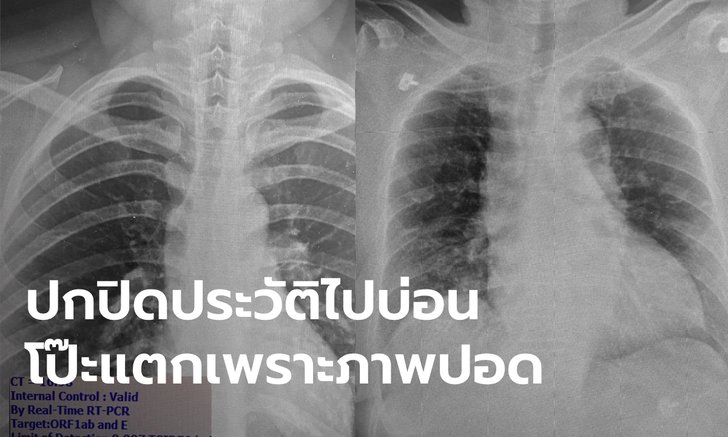

(4 ม.ค.63) นพ.โอภาส พุทธเจริญ หัวหน้าศูนย์โรคอุบัติใหม่ทางคลินิก โรงพยาบาลจุฬาลงกรณ์ สภากาชาดไทย โพสต์เฟซบุ๊ก Opass Putcharoen เป็นภาพปอดของผู้ป่วยโควิด 19 รอบใหม่ พร้อมกับระบุว่า ภาพเอกซเรย์ปอดคนไข้ครั้งนี้ไม่เหมือนกับการระบาดระลอกแรก จนทำให้คนไข้ที่ปกปิดข้อมูล ยอมสารภาพว่าไปบ่อนมา และบ่อนอยู่ใน กทม. นี่เอง รายละเอียดมีดังนี้

- เชื้อแบ่งตัวได้ดีในจมูกและทางเดินหายใจ คนไม่มีอาการจะมีเชื้อในจมูกเยอะมากพร้อมที่จะแพร่กระจายเป็นวงกว้างเวลาไอ จามหรือพูด ในรูปภาพซ้าย ภาพถ่ายปอดผู้ที่ติดเชื้อที่ไม่มีอาการเลย เดินไปเดินมา ใช้ชีวิตเหมือนคนปกติ แต่เชื้อในจมูกค่า CT (cycle threshold) จากเครื่อง PCR บอกว่ามีปริมาณเชื้อในจมูกสูง มากเมื่อเทียบกับคนไข้ที่เคยเห็นในระลอกแรก ดังนั้นถ้าไม่ได้มาตรวจก็แพร่กระจายเชื้อคนอื่นได้อีกมาก

- รูปขวา--เราเริ่มเห็นคนมีอาการไข้หวัดหรือปอดอักเสบมาที่โรงพยาบาล แต่ไม่ยอมบอกประวัติความเสี่ยงเพื่อปกปิดการเดินทาง แพทย์อาจไม่ได้ส่งตรวจหาโควิด เพราะคิดว่าเป็นปอดอักเสบจากเชื้ออื่นที่พบได้บ่อยกว่า

ดังนั้นถ้ามีประวัติไปที่เสี่ยงตัองแจ้งแพทย์เสมอเพื่อแยกออกไปจากคนไข้คนอื่นที่มีโอกาสติดแล้วมีอาการรุนแรงหรืออาจติดต่อไปยังหมอและพยาบาล เมื่อวานมีคนไข้เป็นปอดอักเสบมาตรวจ แต่ไม่ยอมบอกประวัติความเสี่ยงแต่แพทย์เห็นฟิล์มผิดปกติเหมือนปอดอักเสบจากไวรัสเลยส่งตรวจโควิดและตรวจเจอเชื้อ พอเค้นซักประวัติอีกรอบถึงยอมรับว่าไปบ่อนมา ซึ่งเป็นบ่อนใน "กรุงเทพ" นี่เอง